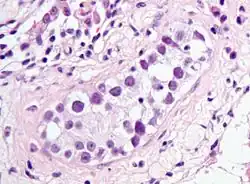

Wewnątrzprzewodowa neoplazja komórek zarodkowych

| Intratubular Germ Cell Neoplasia | |

Wewnątrzprzewodowa neoplazja komórek zarodkowych, obraz mikroskopowy, barwienie H+E | |

Wewnątrzprzewodowa neoplazja komórek zarodkowych (ang. Intratubular Germ Cell Neoplasia, IGCN) – stan przedrakowy, poprzedzający rozwój nasieniaków (złośliwych nowotworów zarodkowych jądra), z wyjątkiem nasieniaka spermatocytowego. Uważa się, że obecność IGCN poprzedza wystąpienie większości guzów zarodkowych jądra u dorosłych (zarówno klasycznych nasieniaków jak i nienasieniaków). Szacuje się, że czas potrzebny do progresji od IGCN do inwazyjnego guza zarodkowego jądra wynosi ok. 5-7 lat. Skumulowane ryzyko wynosi 70% w czasie 7 lat.